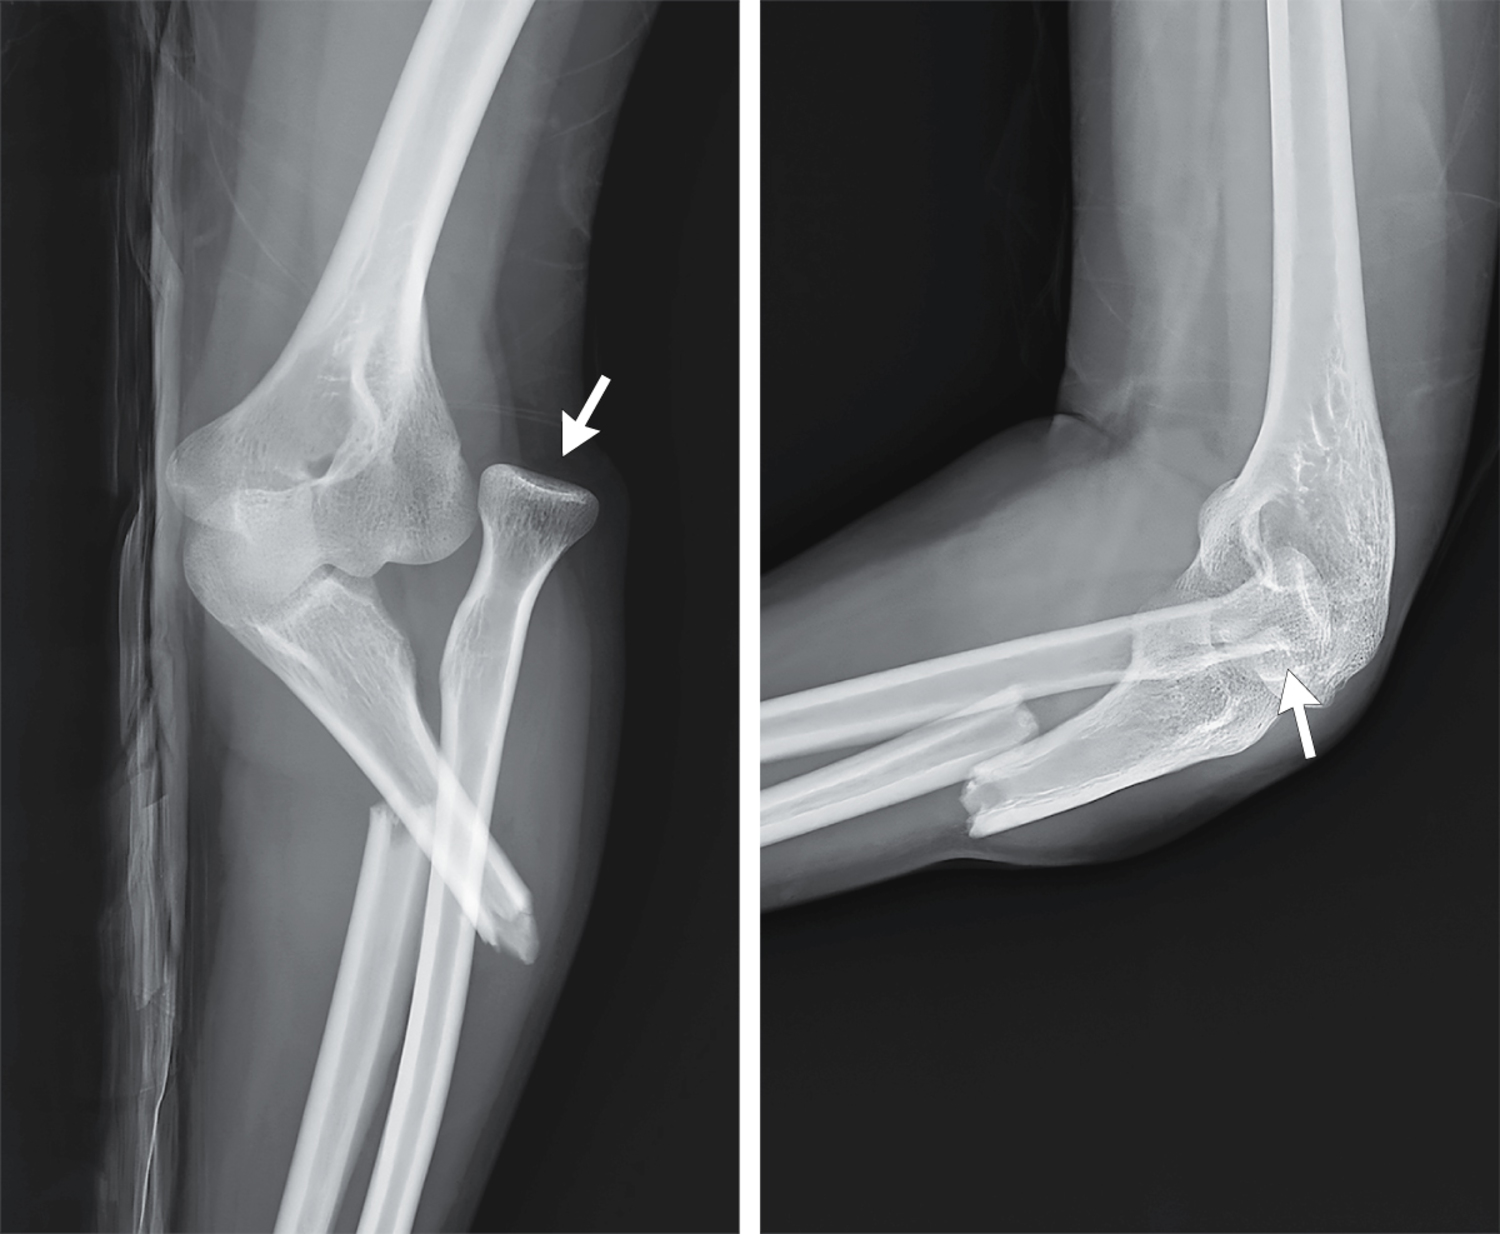

A 26-year-old woman presented with pain in her left elbow after falling on an outstretched hand while ice-skating. Physical examination revealed left lateral elbow swelling and tenderness to palpation, a valgus deformity, and limited range of motion. Which of the following findings are present on the imaging?一名26岁女性在滑冰时摔倒,手掌撑地,随后出现左肘疼痛。体格检查显示左肘外侧肿胀、触痛、外翻畸形以及活动范围受限。以下哪项影像学表现是存在的?

这是一类被称为 Monteggia 骨折脱位 的损伤,其特征是 尺骨近端骨折 合并 肱桡关节脱位。这种骨折通常发生在人摔倒时手掌撑地,前臂处于 极度旋前 位的情况下。早期识别并进行手术干预对于预防 长期功能障碍、桡神经损伤或肘关节僵硬 至关重要。

正确答案:B